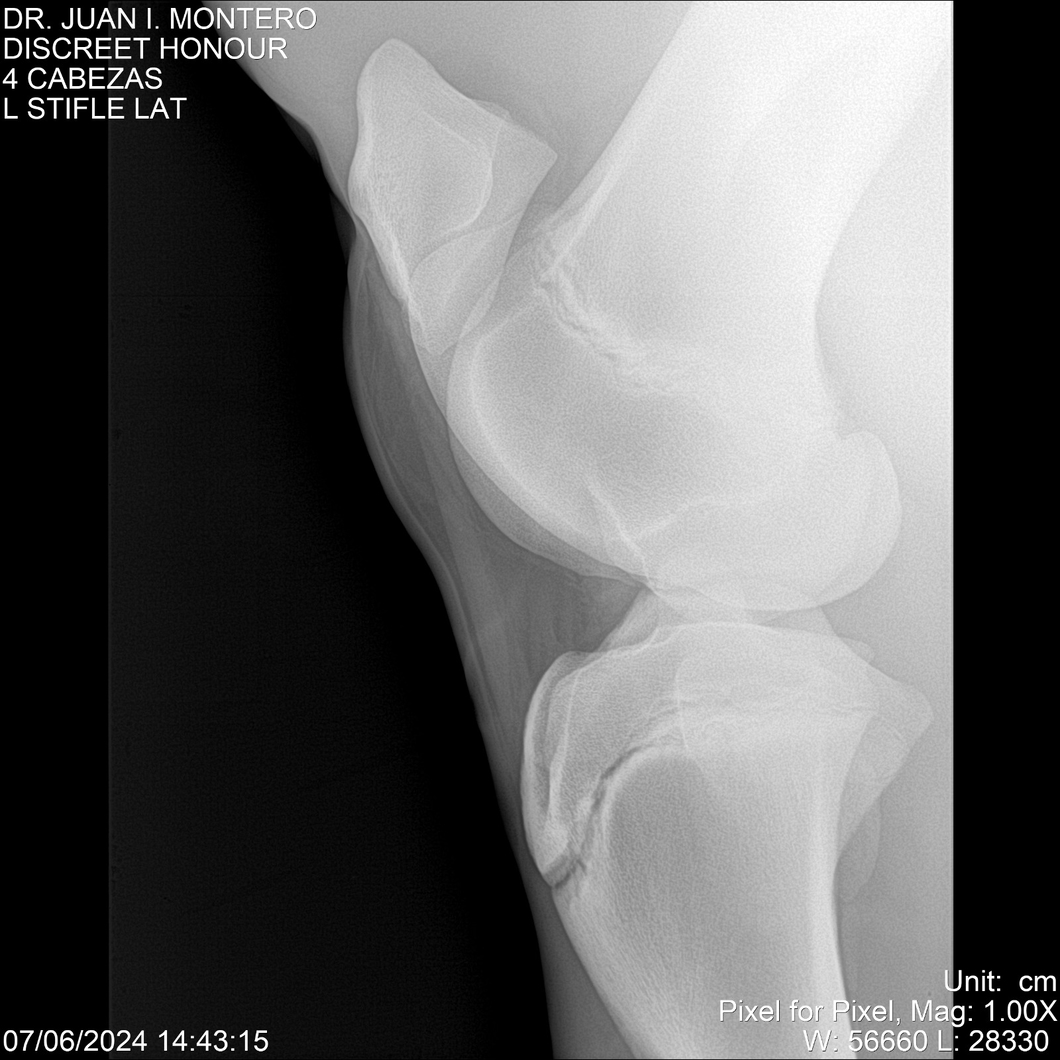

LOTE 6, DISCREET HONOUR 🔥 🔥 🔥 Lote Anterior Volver al remate Lote Siguiente Ficha Contacto Montevideo - Ficha del Lote Identificador: #281093 Categoría: Yeguarizos Montevideo - 82 Visualizaciones ClicData Contacto Empresa: Abelenda N. R., Walter Hugo Nombre*: Teléfono* : E-mail* : Mensaje Enviar Registrese gratis Este contenido Exclusivo está disponible sólo para usuarios registrados Ingresar